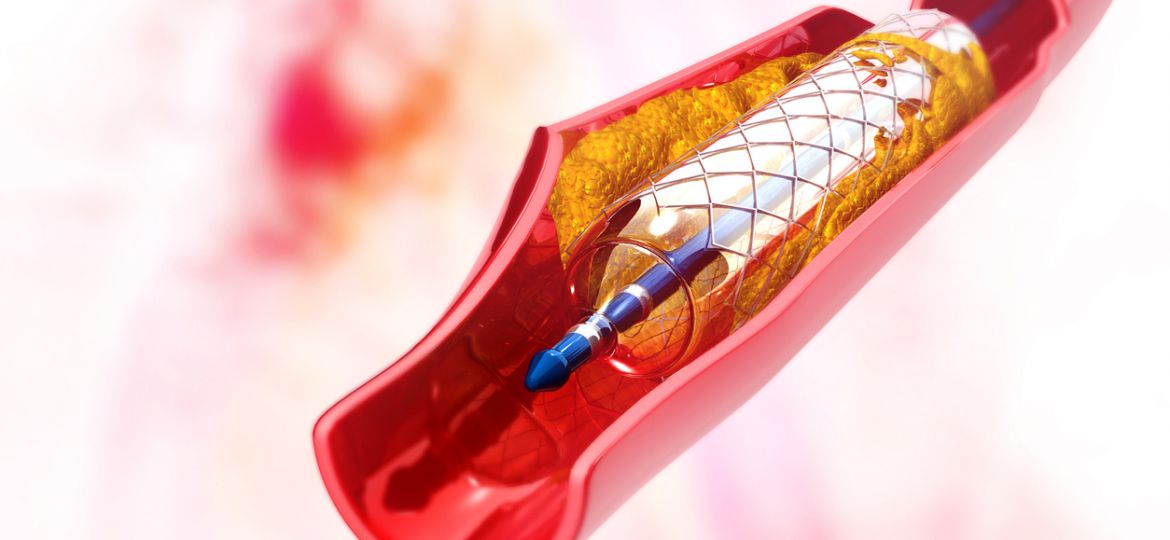

O infarto agudo do miocárdio é a causa mais comum de morte global, sendo responsável por 32% dos óbitos no…